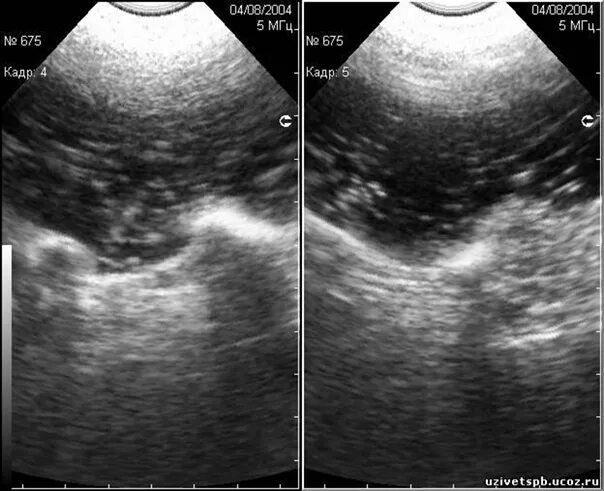

Делают узи желудка или нет